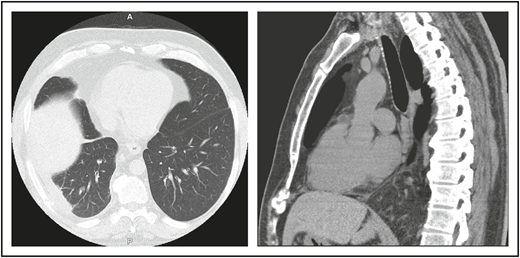

A 46-year-old male contractor who smoked but was previously healthy had acute AIHA. He was treated with prednisone and recovered. This occurred again the following year, and he required blood transfusions. Four years later, AIHA again occurred; he developed a clot in his aorta with thrombosis of his splenic artery, resulting in a splenic infarct. He had a splenectomy and recovered uneventfully. The following year, he developed pneumonia with a large posterior empyema; Streptococcus pneumoniae was cultured (Figure 1). The collection was drained, complicated by a collapsed lung, but he recovered. Six months later, he had a second bacterial pneumonia, and immunoglobulin was measured. These tests showed remarkably low levels of serum immunoglobulins: IgG, 71 mg/dL (normal range, 639-1349); IgA, 6 mg/dL (80-350); and IgM, 15 mg/dL (45-250). He had no protective titers of antibody to any vaccines. Intravenous immunoglobulin replacement was instituted, and the patient experienced no further episodes of either infection or autoimmunity.

(A) The patient in clinical case 1 with several episodes of severe autoimmune hemolytic anemia was only diagnosed with CVID after he had bacterial pneumonia and developed an empyema. (B) Lateral view shows the posterior empyema collection.

A second common reason for a patient to come to the attention of hematologists is the finding of an enlarged spleen, especially in an adult with lymphadenopathy. This was the reason in patient 2, who is now a 46-year-old male professional dog walker. At the age of 31, he was found to have an enlarged spleen together with cervical and axillary lymphadenopathy. Hematology was consulted, and the lymph node was biopsied; pathology revealed that he had noncaseating granuloma. He was then referred to pulmonology and, with this evidence, was diagnosed with sarcoidosis and treated with steroids for some months, but he stopped the treatment. Although he had no obvious respiratory symptoms over the following 15 years, he had a slow decline in lung function, and chest computed tomography showed hilar lymphadenopathy, ground-glass opacities with nodules, and bronchiectatic changes (Figure 2). In 2018, he had acute bacterial pneumonia, became concerned, and found on the internet that granulomata in the lungs and an enlarged spleen might be related to low serum immunoglobulin levels. He asked that this be tested; when this test was performed, he had striking low serum immunoglobulins: IgG, 97 mg/dL; IgA, <5 mg/dL; IgM, 27 mg/dL. However, within the month, he was hospitalized for pneumonia due to metapneumovirus. The diagnosis of CVID was finally made, and immunoglobulin treatment was started. The patient’s spleen remains large.

The patient in clinical case 2 had a slow decline in lung function due to his immune defect, but this was assumed to be due to sarcoidosis. Chest computed tomography showed ground-glass opacities with numerous nodules, hilar lymphadenopathy, and bronchiectatic changes. With granuloma on biopsy, these changes were consistent with granulomatous lymphocytic interstitial lung disease.